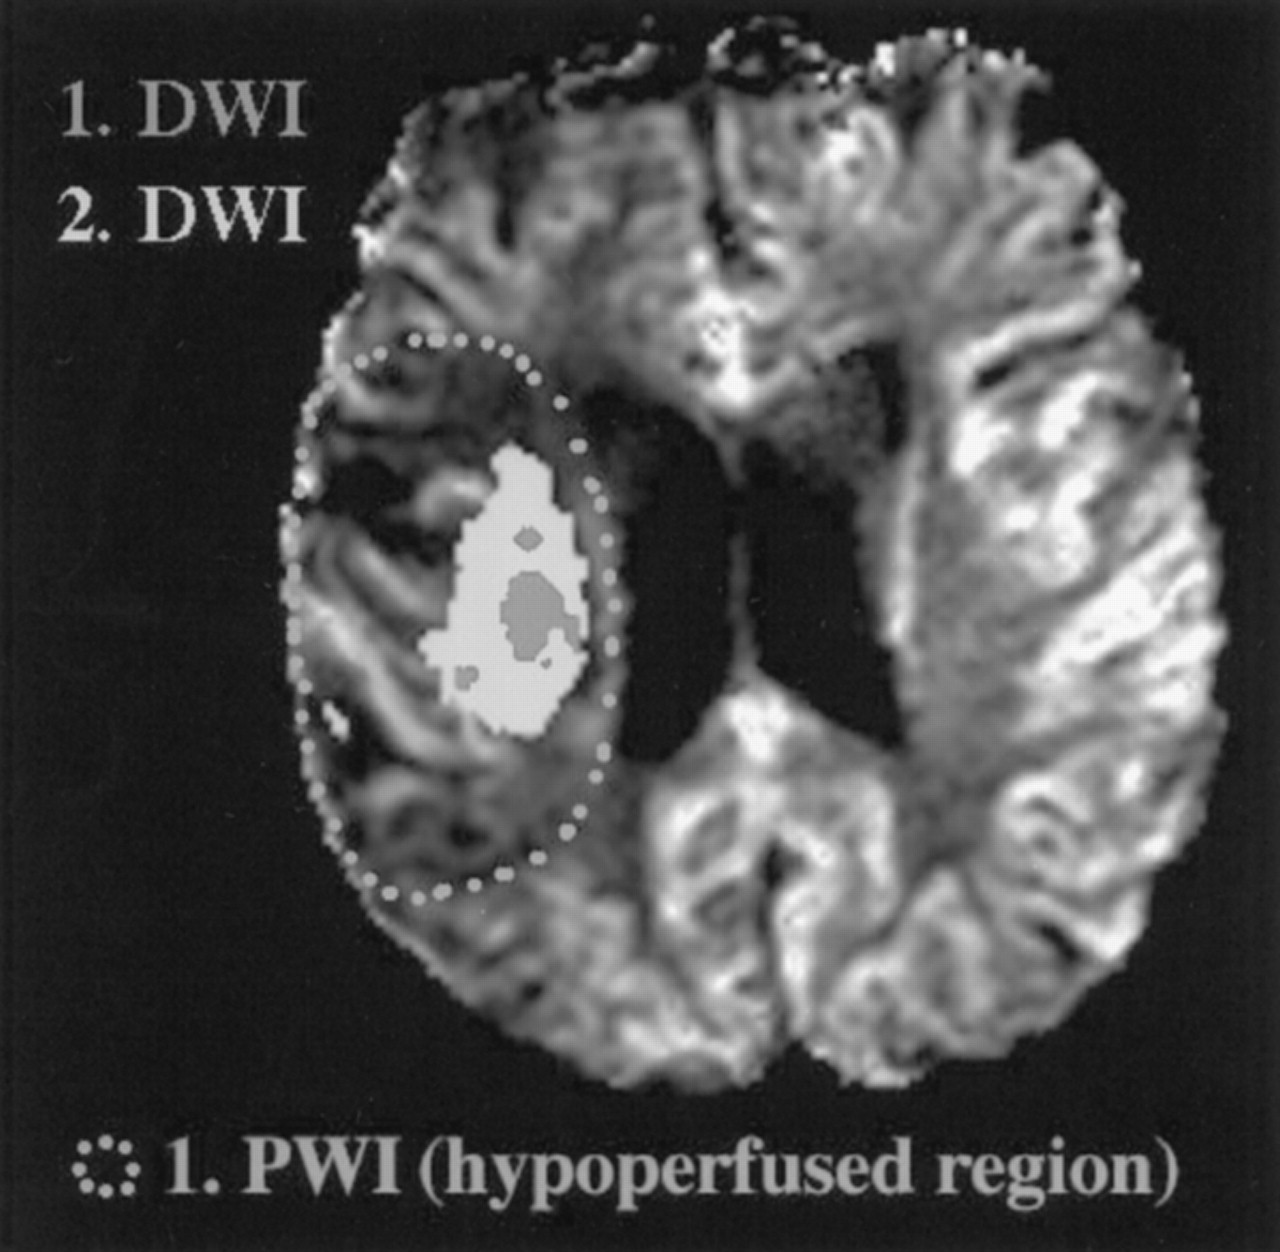

图1所示。相对脑血容量(rCBV)计算三个操作定义的区域(缺血性心、半影和侧控制区域[CControl])在个别病人。曲线下的面积的数字集成(ΔR2之和*)cb v值正比于在正常脑组织都未。后组织浓度时间课程钆注射后,我们评估了三种不同的端点rCBV地图计算来确定哪个终点将最大化正常和缺血大脑区域之间的差异。在面板我们综合曲线下的面积正常控制区域的峰值,然后,时间点是定义的操作也用作截止半影和核心区域(初始rCBV,面板)。在面板b我们集成,计算曲线下的面积的峰值的三个区域(rCBV峰值),并在面板c我们综合的组织浓度时间曲线返回一个局部最小值(总rCBV),这称为第一遍的结束。

基于先前建立缺血半影和出版的特点,1,5,11我们开发了一个操作性定义的组织梗塞的风险使用回顾性方法的进展。第一个发现的病变扩散研究表明在我们的操作模型缺血性核心(图3和图4⇓)。初始扩散之间的不匹配区域病变及其扩展了后续醉酒驾车研究后的24到72小时第一个定义操作半影。从第一天使用灌注研究,指标CBV(初始rCBV、峰值rCBV总rCBV)和流(rCBF) rMTT,以及ADC值测定在三个地区(见定义图3和图4⇓):1)酒后病变时间点1(代表我们的操作缺血性核心),2)之间的不匹配区域首次和后续醉酒驾车研究(代表我们的操作半影),和3)侧半球,影响严重的地区反映第一醉酒驾车病变程度和解剖位置。镜子地区必须在10%的醉酒驾车病变的大小必须在同一时间点1,对侧半球的解剖定位。排除可能从intrasulcal工件或蛛网膜下腔CSF,我们手动放置这些地区所有片上,他们可以被识别,并计算意味着跨片(加权体素)的数量为每个定义的操作区域。

图3。操作模型定义缺血半影。第一个发现的病变扩散研究表明该地区能源的衰竭和类似于操作缺血性核心在我们的模型中。这种扩散的扩大病变(后续扩散研究)到大hypoperfused地区运营半影在这项研究。